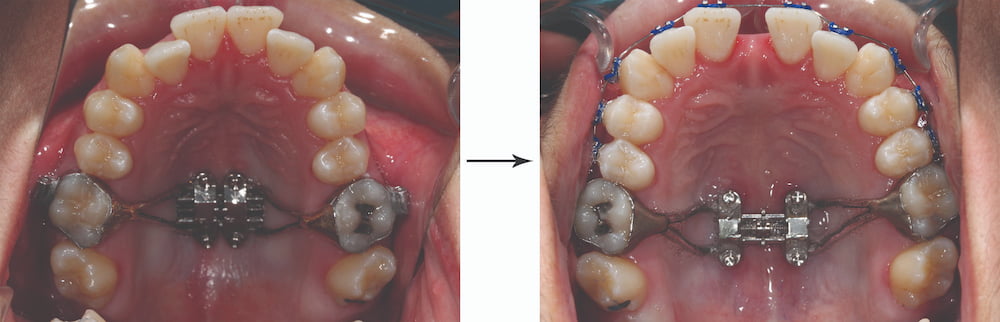

Before-and-after images of an MSE2 MARPE expander at Elara Orthodontics in Richmond or Houston, TX, showing dental arch changes.